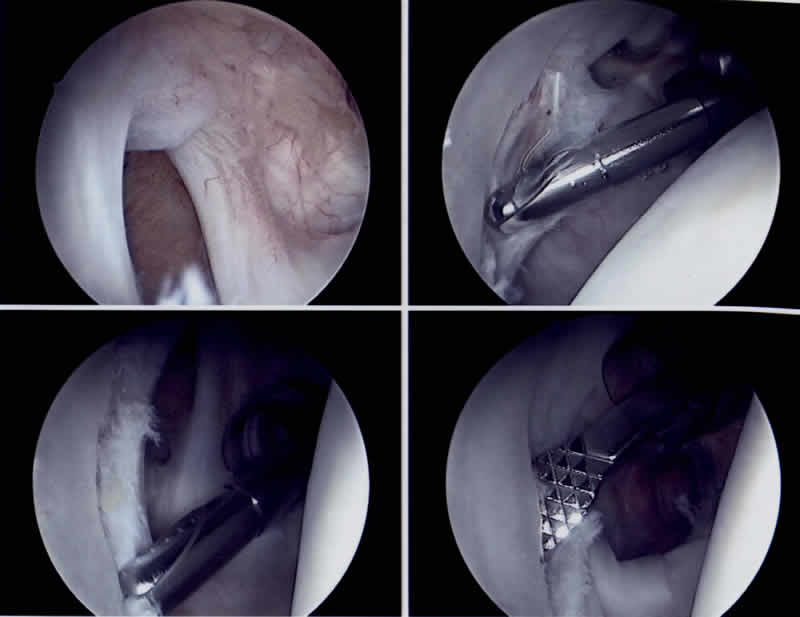

Ziel der Operation ist es, die normale Schultergelenksfunktion weitestgehend durch die Wiederherstellung der normalen Anatomie zu garantieren, was jedoch infolge des unfallbedingten Gewebeverlustes nicht immer möglich ist. Der optimale Zeitpunkt für eine operative Stabilisierung ist der Zustand nach der traumatischen Erstluxation, da dann der anatomische Schaden vergleichsweise am geringsten ist und die zur Heilung notwendigen Gewebebedingungen ideal sind. Wir empfehlen diese Operation vorallem den jungen Patienten und Patientinnen mit häufigen sportlichen Wurfsportaktivitäten (Volleyball, Handball, Basketball, Beach Volleyball, etc.). Diese Operation wird heute unter Berücksichtigung verschiedener Faktoren, fast immer arthroskopisch, das heisst minmal invasiv durchgeführt.